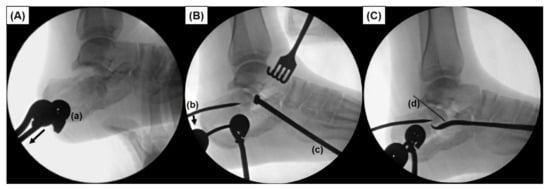

2.2. Surgical Technique